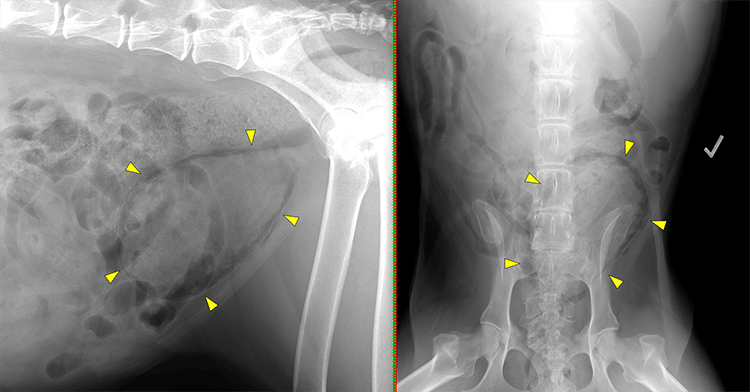

Figure 2: Lateral and ventrodorsal radiographs of a diabetic patient with emphysematous cystitis. Note the irregular peripheral gas lucencies associated with the bladder, indicating intramural emphysema secondary to infection with gas-producing bacteria (yellow arrowheads).